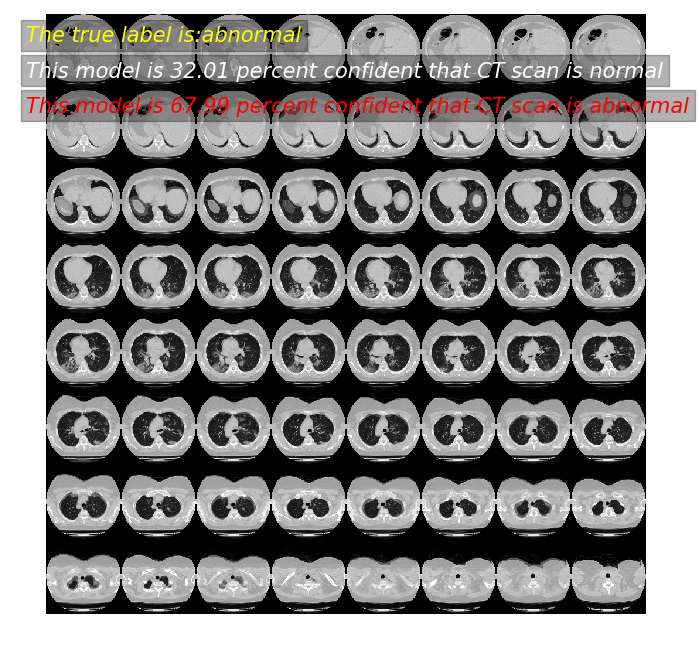

[37]:

predictor(11)

模型预测: 32.01 概率,这张CT normal

模型预测: 67.99 概率,这张CT abnormal

真实标签为: abnormal

../../_images/practices_cv_3D_image_classification_from_CT_scans_32_1.png